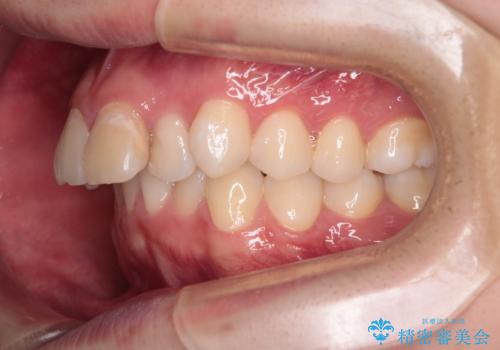

- 前歯が出ていることを主訴に来院されました。

臼歯関係が上顎前突傾向のため、上顎小臼歯を抜歯してインビザラインにて治療を行いました。

臼歯の咬合を作るために治療終盤ではゴムかけを行なっています。